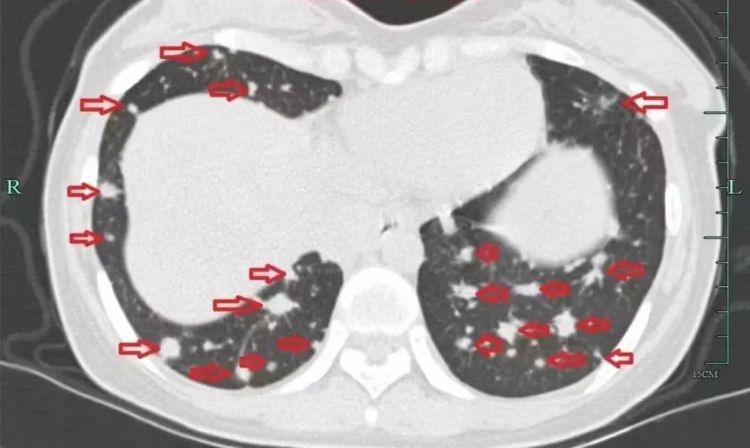

治疗前

入院后,小谢完善了抽血化验及肺部CT、肝脏磁共振等检查,但结果却极其凶险,肺部转移灶如“满天星”,肝脏肿块压迫胆管导致胆红素水平飙升,整个人都“黄”得一塌糊涂。